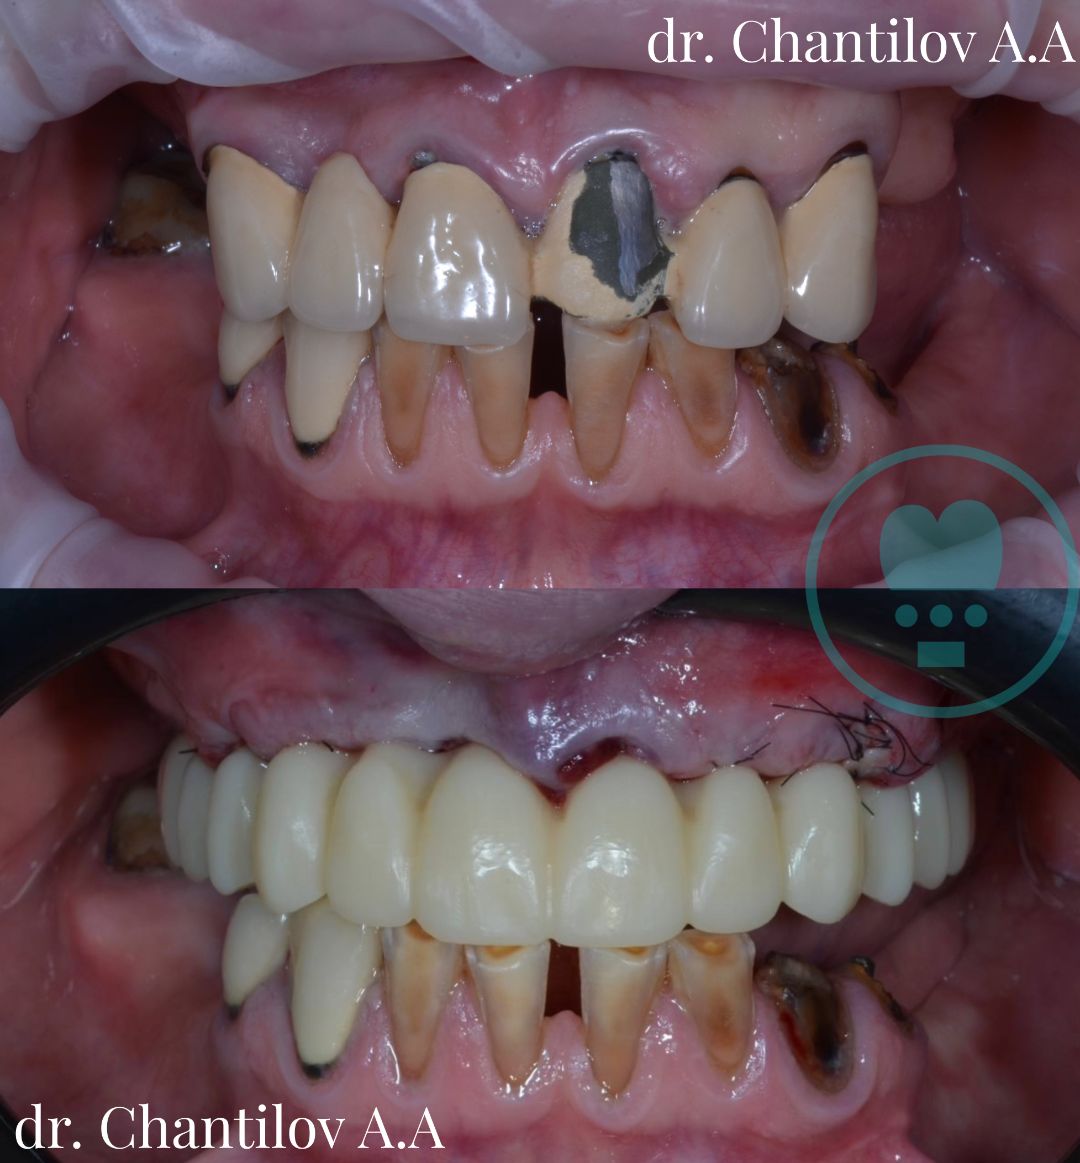

Имплантация зубов челюсти - фото до и после